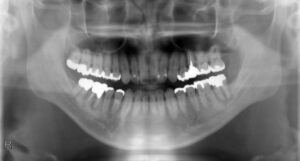

下顎大臼歯1本欠損症例

BEFORE AFTER 50歳男性/下顎1本欠損/インプラント埋込手術 【治療内容】 左下第二大臼歯が炎症を起こし、保…